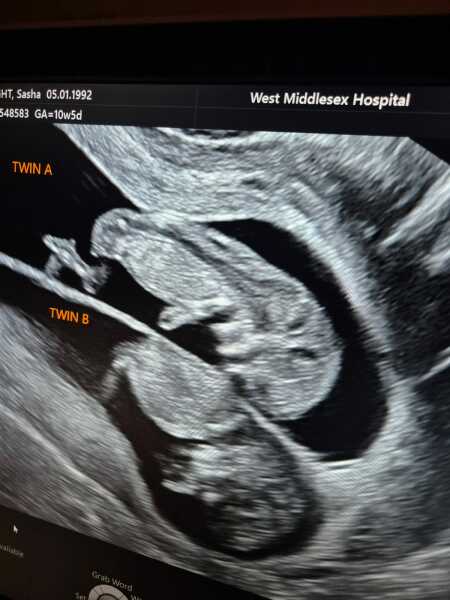

ThisPinkHare · 24/07/2025 00:33

So this happened

Silent miscarriage